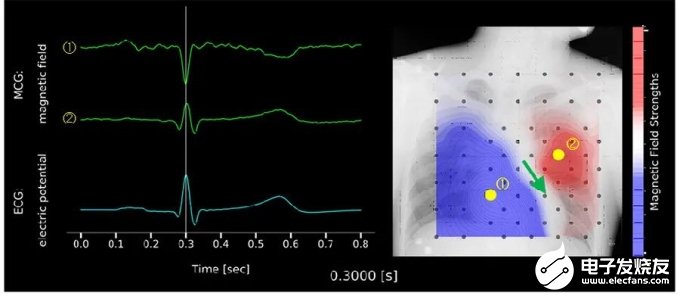

使用TDK的64ch MR磁性傳感器進(jìn)行心臟磁場(chǎng)分布測(cè)量及可視化的示例如圖7所示。重疊胸部X光片后,藍(lán)色波形映射了心電圖(ECG)、綠色波形映射了心磁圖(MCG),而照片則映射了心臟的磁場(chǎng)分布。黑色點(diǎn)為傳感器信道,心磁圖波形為通過以黃色點(diǎn)(①②)表示的傳感器信道得到的磁場(chǎng)強(qiáng)度時(shí)間波形。之所以波形峰值之間方向相反是因?yàn)榇帕€方向不同。

? ? ? ?照片中與天氣圖等壓線類似的白色閉合曲線所示為,與心電圖R波相對(duì)應(yīng),且與測(cè)量時(shí)心臟周圍相同磁場(chǎng)強(qiáng)度相結(jié)合的等磁線。紅色以及藍(lán)色部分表示磁力線方向不同。紅色部分表示磁力線的流出方向,藍(lán)色部分則表示磁力線的流入方向。心電圖R波所示為心室收縮過程,通過磁場(chǎng)分布與磁力線朝向以及右手螺旋定則,此時(shí)的心臟活動(dòng)電流可推定為沿綠色箭頭方向流動(dòng)。

圖7 通過64ch MR磁性傳感器陣列測(cè)量并可視化心臟磁場(chǎng)分布的示例